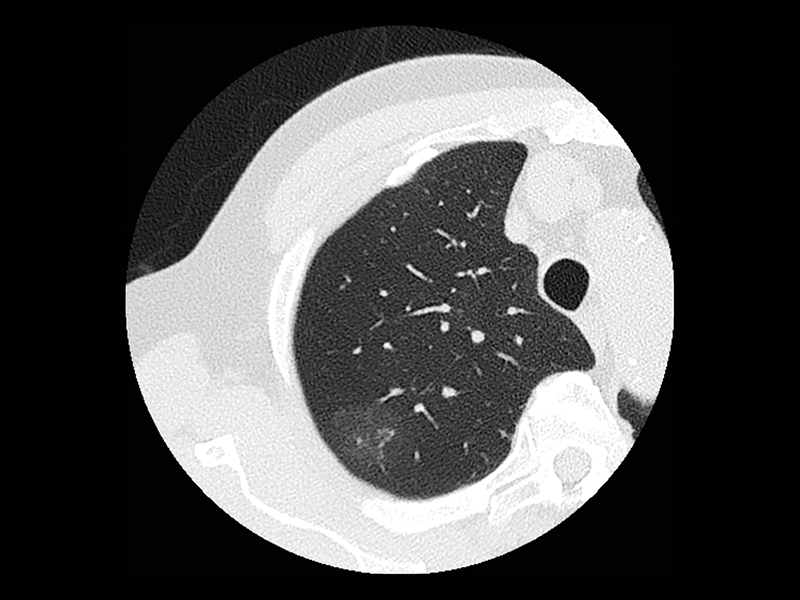

Non-tuberculous mycobacteria

Intraoperative oxygen desaturation(Left)